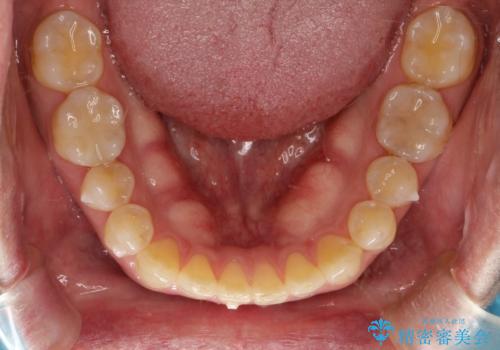

前歯の隙間 インビザラインにて整った歯並びへ

- 前歯の隙間が気になるとのことで来院されました。

インビザラインにて矯正治療を行うこととしました。

下の歯と歯の間にわずかに隙間をつくり、上の前歯の隙間を閉じました。